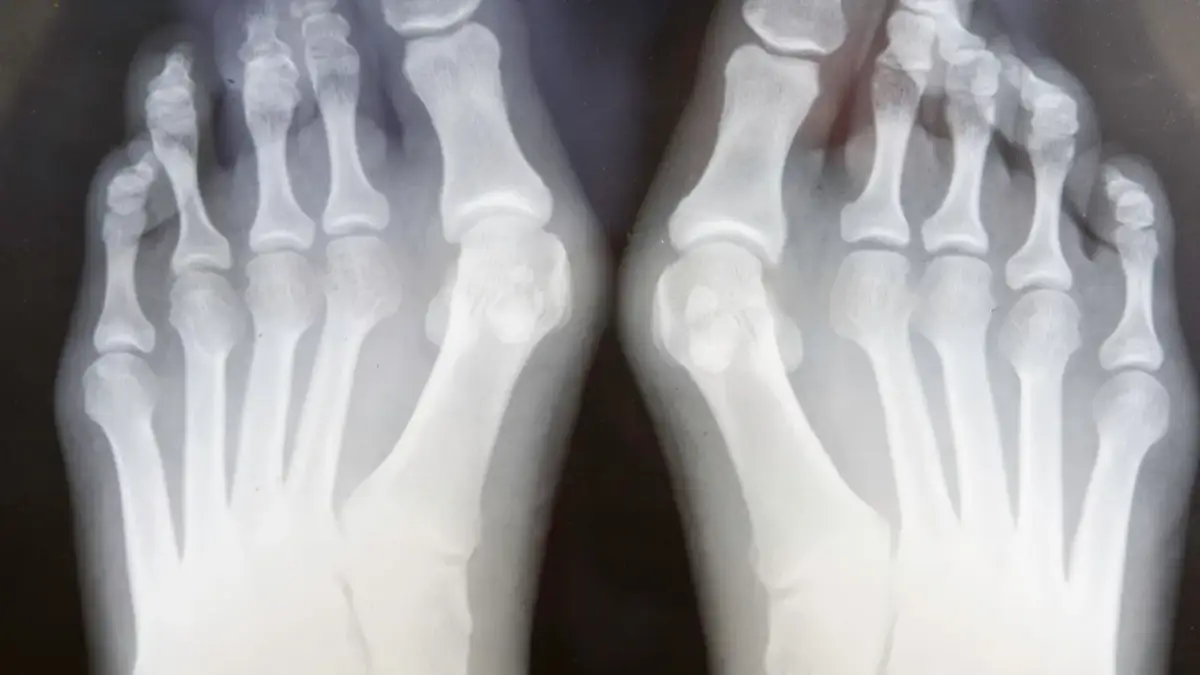

Aparaty korekcyjne na haluksy to mechaniczne urządzenia, które pomagają przywrócić prawidłową pozycję dużego palca stopy. Działają one poprzez delikatne naciskanie na palec i stabilizację stopy, co może zmniejszać ból oraz dyskomfort związany z tą deformacją. Użytkowanie tych aparatów może przyczynić się do poprawy jakości życia, zwłaszcza dla osób, które zmagają się z codziennymi trudnościami w doborze obuwia.